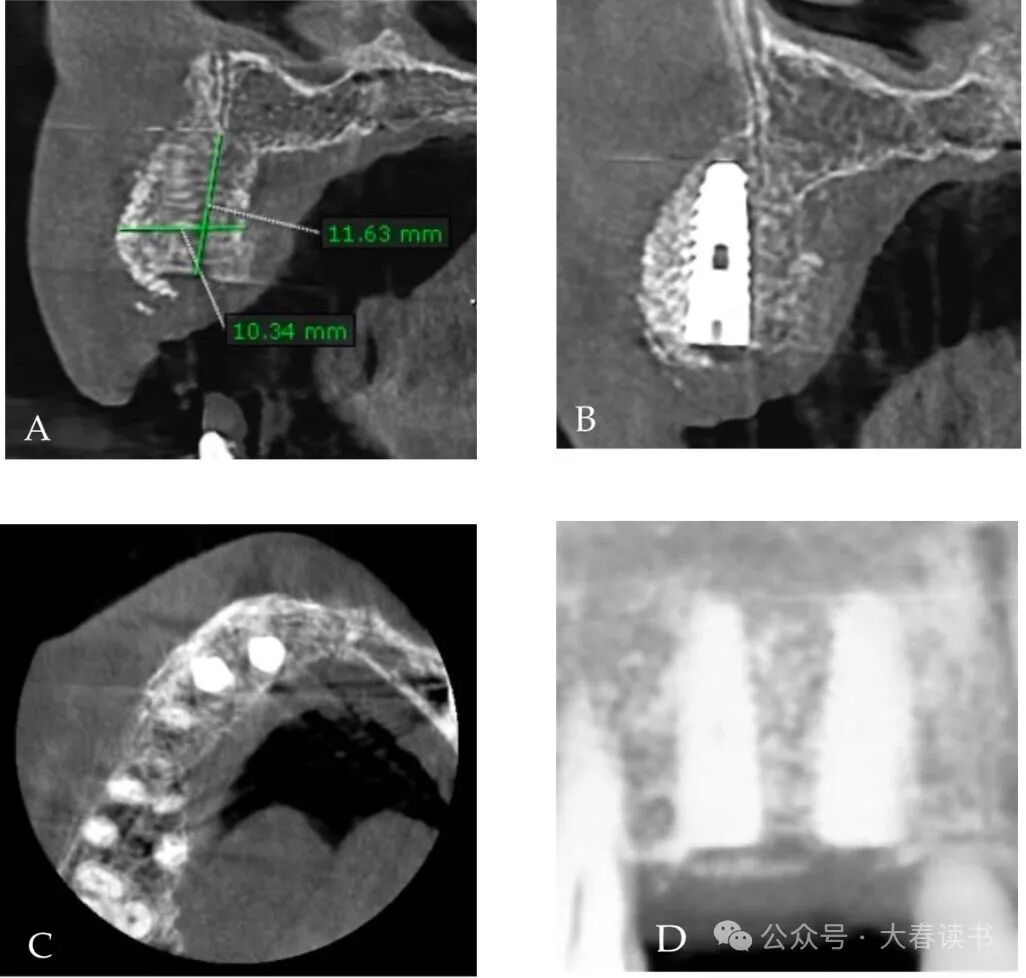

Figure 2: Initial CBCT: The defect area measures approximately 4.19mm x 4.2mm.

Figure 11: CBCT image after implant placement.